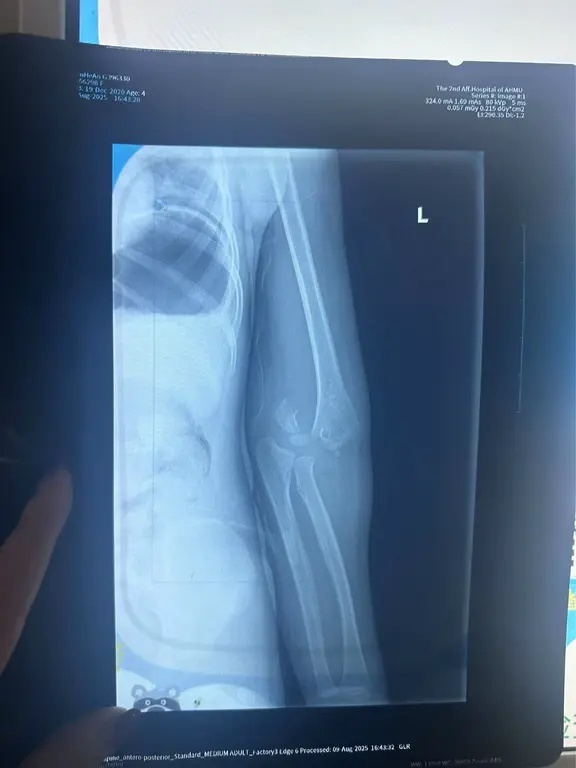

监控视频画面显示,当时一位戴眼镜身着深色上衣的男子距离出事女孩最近,他发现这一情况后,赶紧拉住还在旋转的器械,并试图搭救女孩。随后,妻子带着受伤的孩子打车就医。后经陈先生了解,这位好心大哥还从地下车库开了车出来,准备送母女二人去医院,但因为当时妻子已经打车,双方便没有碰上。据安徽省儿童医院诊断显示,孩子左肱骨远端骨折。

医院诊断显示孩子左肱骨远端骨折。 图/受访者提供